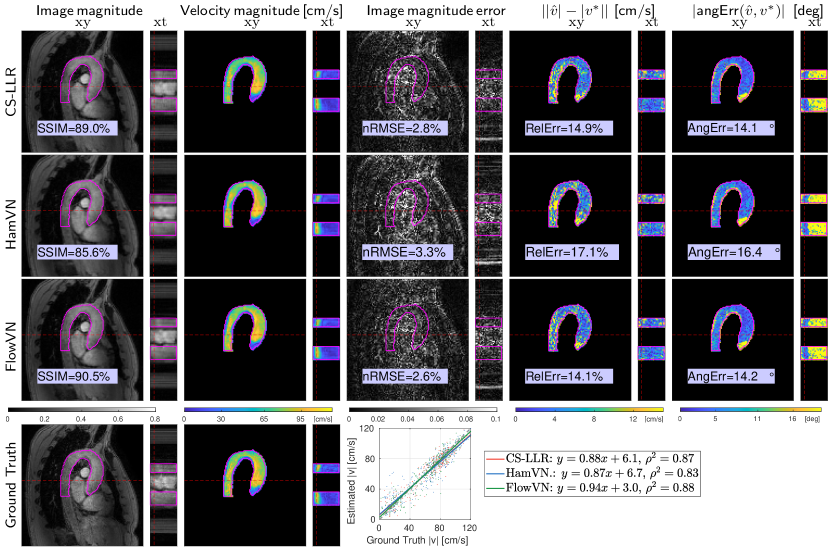

Reconstructed image magnitudes (for a single velocity encoding component), estimated velocity magnitudes and their errors of a healthy volunteer data for acceleration factor =14 are illustrated in Fig. 3 for retrospectively undersampled data. Compared to CS-LLR and HamVN, the proposed FlowVN provides better reconstruction accuracy in terms of image magnitude and velocities. Scatter plot and correlation analysis further suggest that the velocity magnitude image estimated via FlowVN is in better agreement with ground truth. As shown in Supplementary Table 2 these observations extend to other acceleration factors (6–22) as tested on 7 healthy volunteers.

For simulated retrospective undersampling experiments, we used 2 PI data and simulate a pseudo-radial Golden angle sampling pattern 39 with acceleration factors of 6 to 22.

For each undersampling factor we evaluated the nRMSE of the image magnitude, the relative error (RelErr) of velocity magnitudes inside the aorta and the angular error (AngErr) of the estimated velocity vectors:

Additionally, we report the structural similarity index (SSIM) 46 with = on the reconstructed magnitude images.